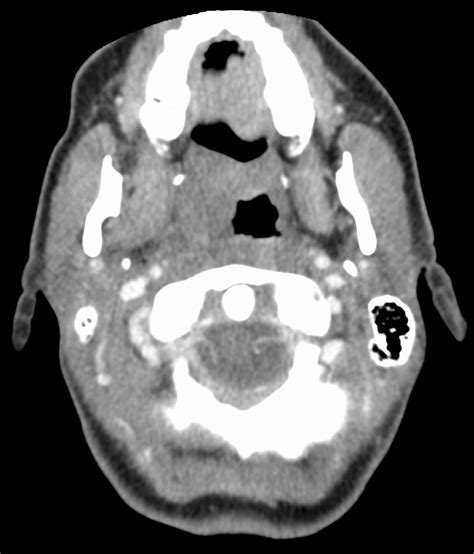

The Journey to a CT-FFR Result: What Happens?

Curious about how you actually get a CT-FFR result ? It’s a pretty fascinating journey, guys, and it all starts with a standard, non-invasive test: a Coronary CT Angiography, or CCTA. You might have already heard of this or even had one done. During a CCTA, a special dye (contrast material) is injected into your bloodstream, and then you lie down in a CT scanner. This scanner takes incredibly detailed, three-dimensional images of your heart and the coronary arteries that supply it with blood. These images show the anatomy of your arteries – if there are any narrowings, blockages, or other structural issues. Now, here’s where the magic for CT-FFR happens. Once your CCTA is complete, the images aren’t just read by a radiologist; they are sent to a specialized lab or processed using sophisticated software. This software, often powered by advanced computational fluid dynamics (CFD) models and artificial intelligence, takes the anatomical data from your CCTA and simulates blood flow through your coronary arteries. It literally builds a virtual model of your heart and its vessels and then calculates how blood would flow through them under various conditions. This computational analysis can take anywhere from a few hours to a day, depending on the lab and the complexity of the case. The beauty of this process is that it doesn’t require any additional procedures, injections, or discomfort for you beyond the initial CCTA. It’s all done off-site using the data already collected. This means you don’t have to undergo another invasive test, which is a huge win for patient comfort and safety. Once the analysis is complete, the software provides the FFR values for each segment of your coronary arteries, highlighting any areas where blood flow might be functionally impaired. These results are then sent back to your cardiologist, who will interpret them in conjunction with your medical history, symptoms, and other diagnostic findings. The entire process, from your initial CCTA to receiving the CT-FFR results, is designed to be as seamless and efficient as possible, providing your healthcare team with invaluable information to guide your treatment plan. This innovative approach allows for a much clearer picture of your heart’s health, moving beyond just seeing a blockage to understanding its true impact on blood flow. It’s a remarkable leap forward in cardiac diagnostics, providing unparalleled insights without putting you through additional invasive procedures. The precision and detail offered by this computational analysis are truly astounding, giving doctors a level of insight that was previously only available through much more involved methods. So, when you get a CT-FFR, you’re not just getting a number; you’re getting a meticulously calculated, non-invasive assessment of your heart’s functional blood flow, helping your care team make the most informed decisions possible for your long-term well-being. It’s all about getting you the best care with the least amount of fuss, making your health journey smoother and more predictable.